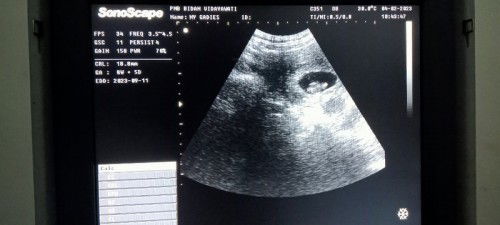

My Orders

Hi moms,permisi mau bertanya.. apakah disini ada yg mengalami hal serupa dgn saya? HPHT saya 23 nov 2022, di puskes dihitung ±sdh 12 weeks tapi ternyata selisih 2 weeks,di usg hitungan nya baru 10weeks mom. HPL dari puskes 31 agustus HPL dari bidan usg 11 september. dalam kasus spt ini,sebaiknya saya mengikuti HPL yg mana ya moms? note : ini foto usg saya 2minggu lalu pas hamil 8W 5D jd skrg sy sdh 10W terimakasih🥰🙏 #seriusnanya #bantusharing #firstmom #firstbaby